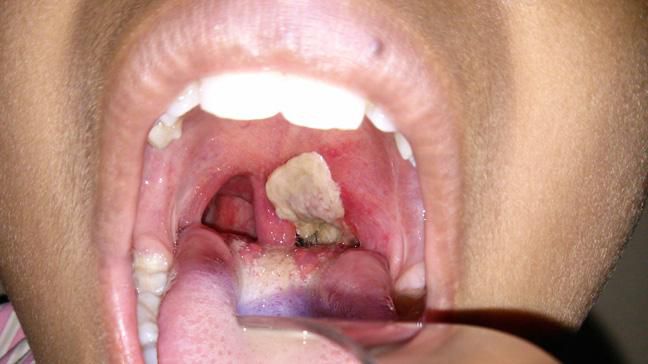

Kano State has recorded over 7,000 cases of diphtheria [Healthline]